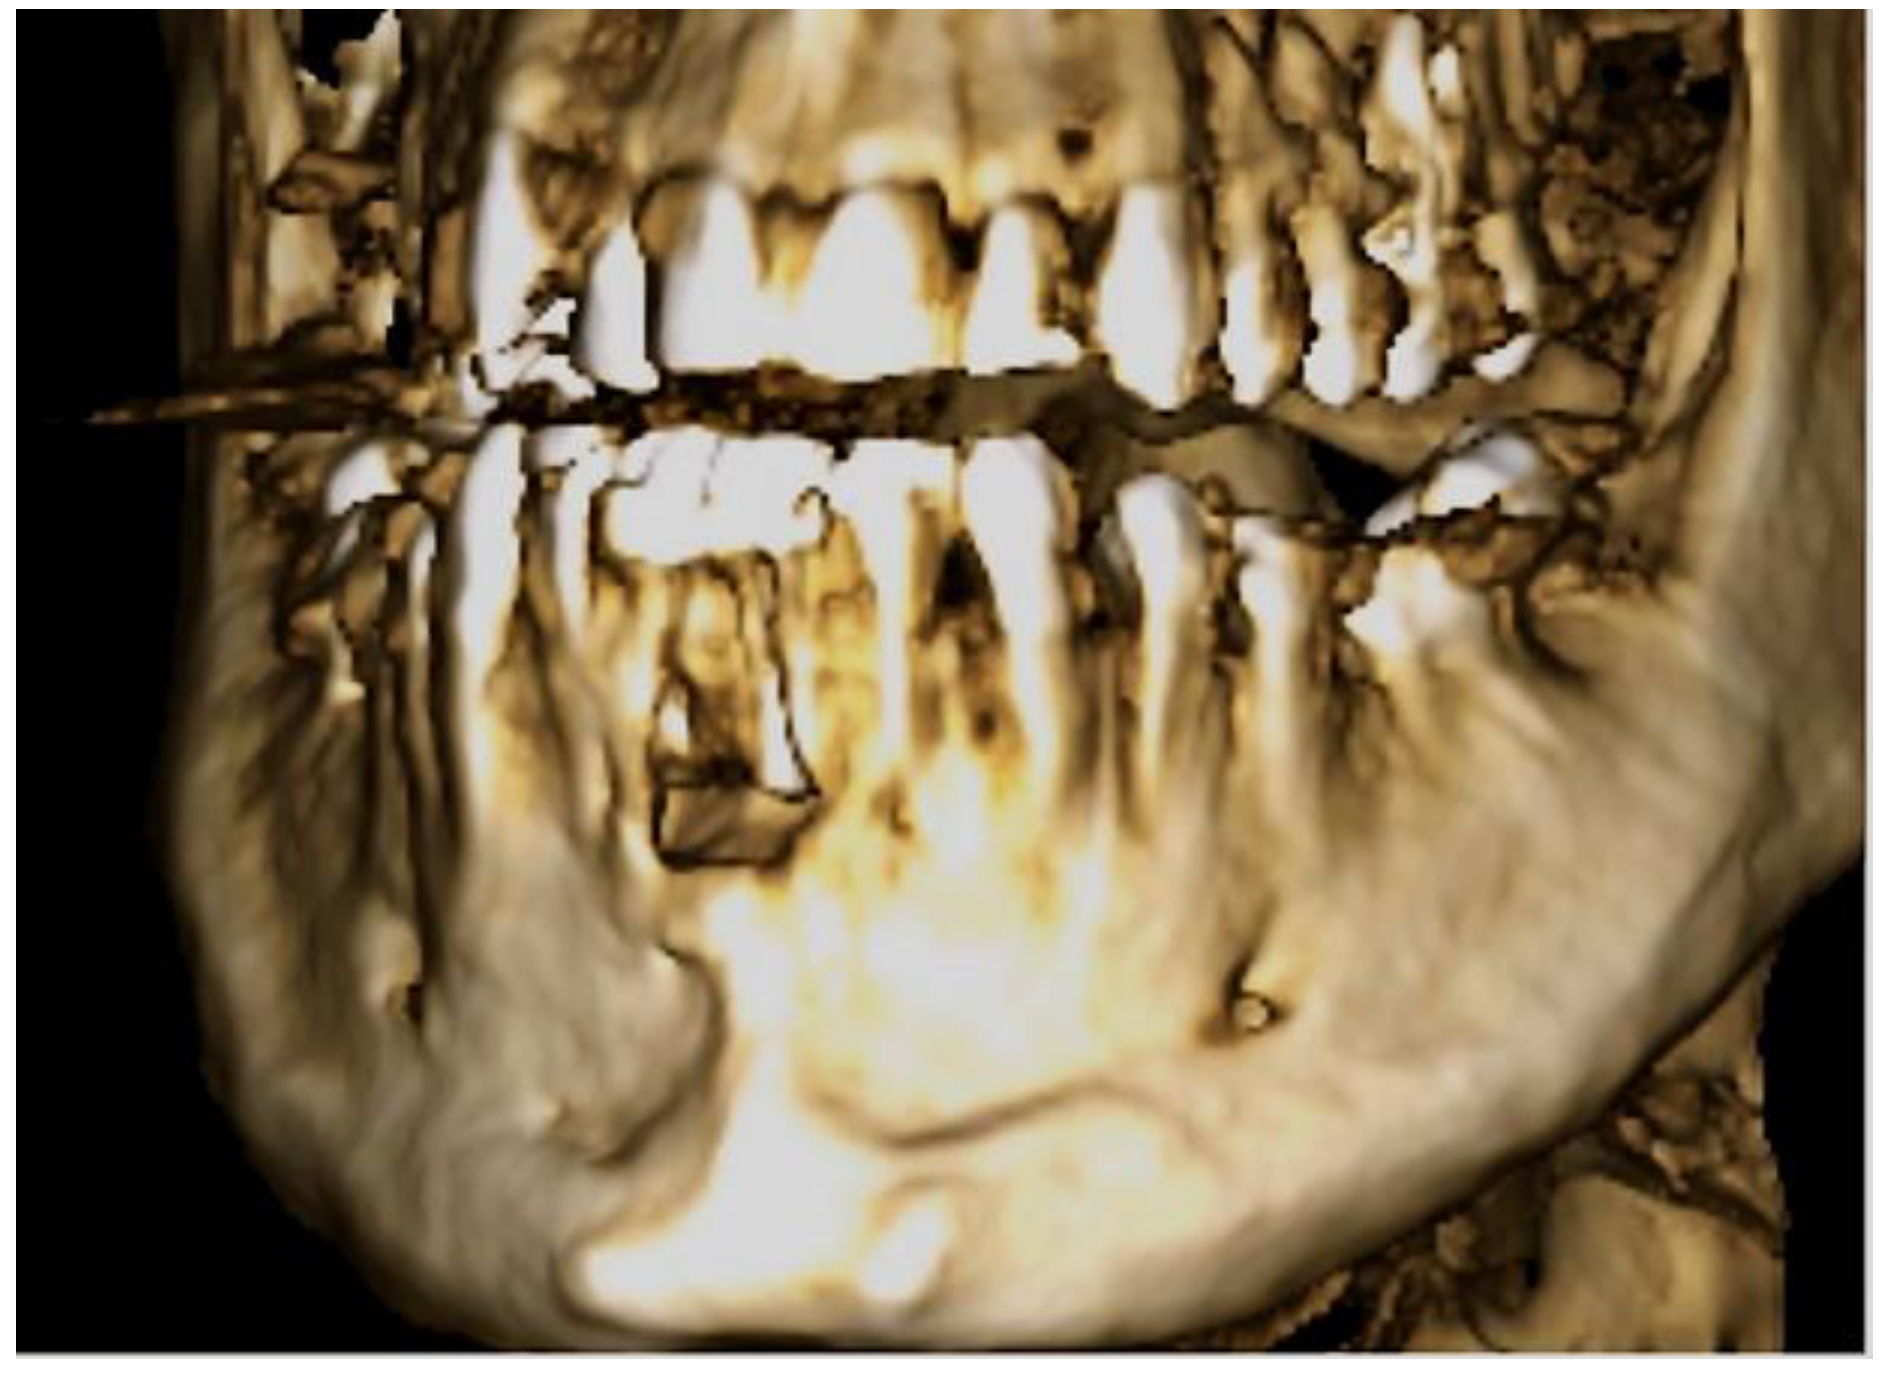

2. Case Description

3. Clinical Procedure and Outcome